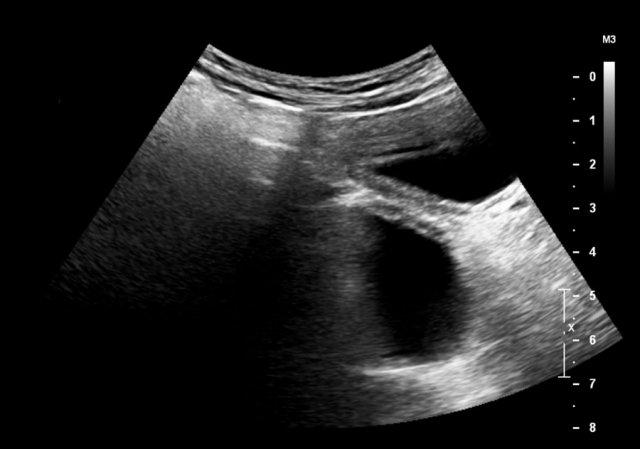

Đây là hình ảnh một nang được phát hiện trước sinh, được xác nhận sau khi sinh ở một bé gái sơ sinh.

Quan sát thấy một nang có mức dịch-dịch (fluid-fluid level).

Trong phẫu thuật, phát hiện xoắn buồng trứng trái.